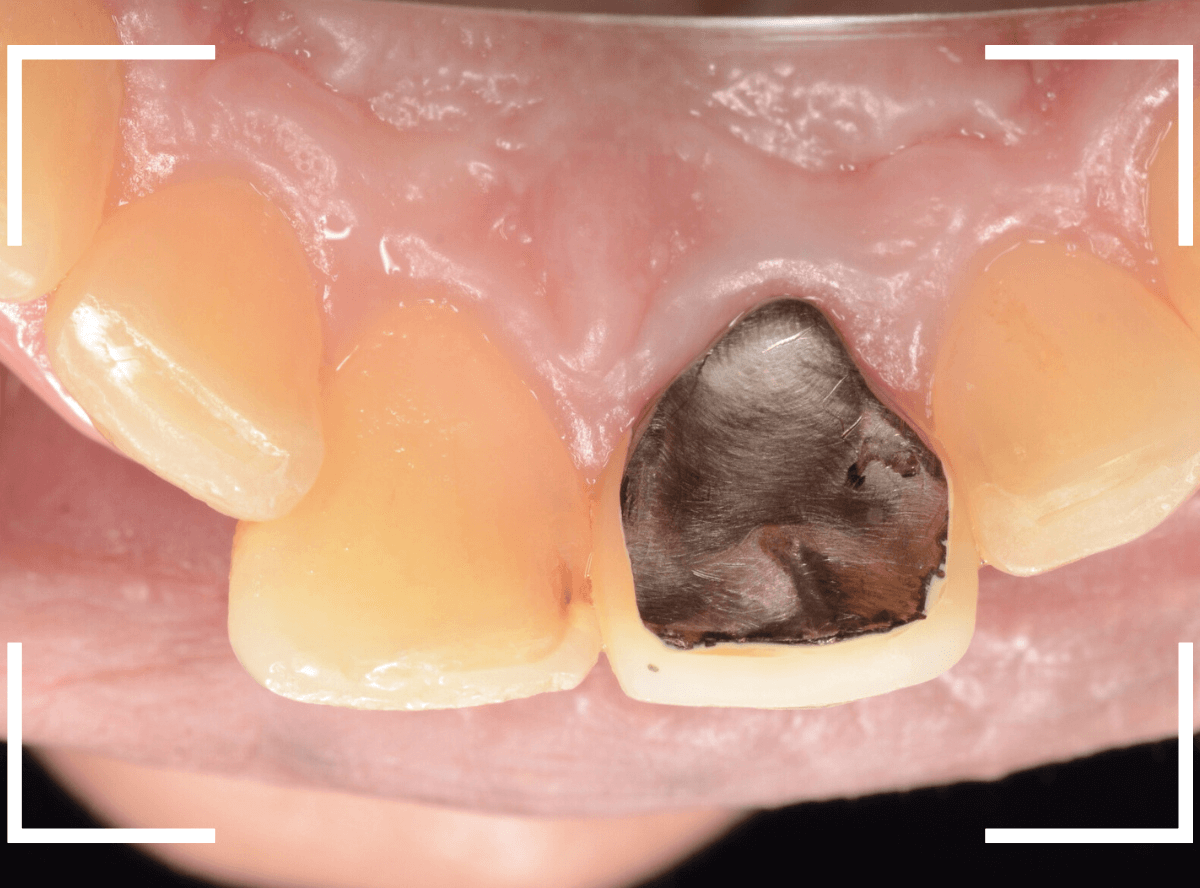

歯を裏側から見たところです。

幸い、見える部分に虫歯が

さし歯と歯肉の間に虫歯ができているのがわかります。

歯の奥まで虫歯が進んでいるのか、浅い虫歯ですんでいるのかは治療をしながら調べていく必要があります。

さし歯を外すと、金属の土台(メタル・コア)が出てきました。

慎重に土台を外して、中を調べます。